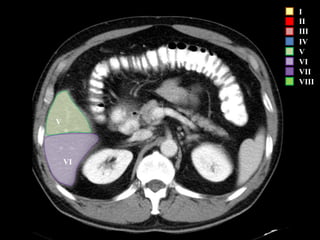

COUINAUD asignó un sistema de numeración para definir la segmentación

hepática.

I

II

III

IV

V

VI

VII

VIII

IVa

I – Entre cava y porta

II – el más superior de los izquierdos

III – Por debajo del II

IV – por delante de la vesícula

V – por detrás de la vesícula

VI – relación con riñón derecho

VII – el más posterior de los segmentos superiores

VIII – domo hepático

Las claves de la segm. Hepática